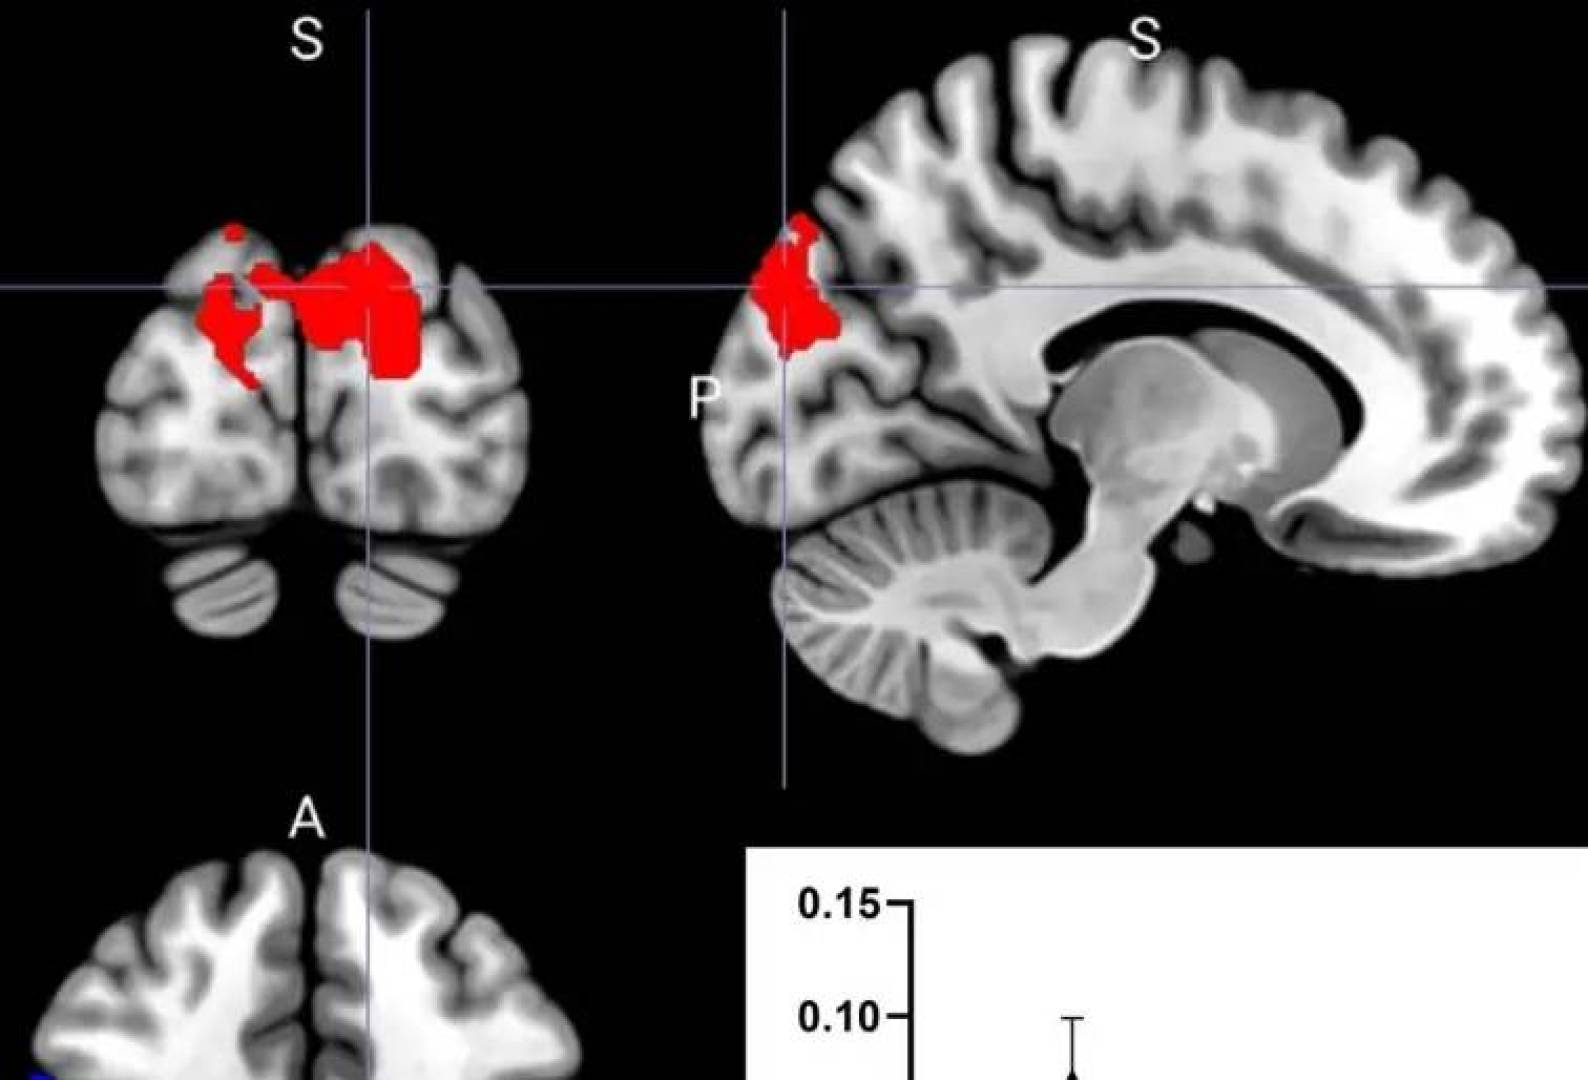

طريقة تناول البروبيوتيك—كبسولات أم مسحوق—تؤثر بشكل مختلف على الدماغ

أظهرت دراسة جديدة من جامعة أوريبرو Örebro University أن شكل تناول —سواء كبسولات أو مسحوق—يؤثر البروبيوتيك على كيفية تأثيره على الدماغ. تم نشر…